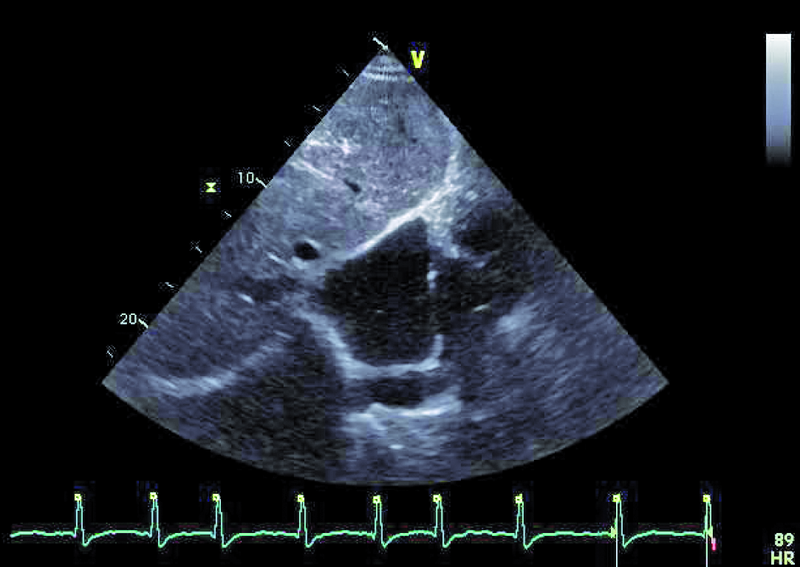

Mężczyzna, lat 31, z wrodzoną wadą serca o typie serca jednokomorowego, zastawkowego i podzastawkowego zwężenia tętnicy płucnej przeszedł w siódmym roku życia zabieg korekcji wady metodą Fontana-Linsa w ośrodku za granicą. Chory od kilku lat gorzej tolerował wysiłek. Rozpoznano napadowe, a następnie utrwalone migotanie przedsionków. Zdarzały się także obrzęki kończyn dolnych, powiększenie obwodu brzucha. Chory negował występowanie sinicy. W badaniu fizykalnym stwierdzono u niego szmer holosystoliczny nad sercem (3/6 w skali Levina), płyn w jamie opłucnej oraz wodobrzusze. Zwrócono uwagę, że w ostatnich latach saturacja spoczynkowa zmniejszyła się z 97 do 90%, a maksymalne zużycie tlenu w teście ergospirometrycznym wyniosło 13,8 ml/kg/min, co stanowiło 31% wartości należnej dla płci i wieku. Stwierdzono silnie wyrażone cechy zespołu enteropatii z hipoproteinemią. W chwili hospitalizacji leczony był dwoma środkami moczopędnymi, beta-adrenolitykiem oraz inhibitorem ACE. Otrzymywał także leczenie przeciwkrzepliwe. Wobec złego stanu ogólnego pacjenta wykonano cewnikowanie serca, stwierdzając ciśnienie w prawym przedsionku 13 mm Hg, średnie ciśnienie w tętnicach płucnych 14 mm Hg, opór płucny 0,2 j.W. Prawy przedsionek był w badaniach istotnie powiększony. Stwierdzano także poszerzenie żyły głównej dolnej (do 36 mm) z cechami samoistnego kontrastowania.

Operację Fontana, będącą rodzajem zabiegu paliatywnego, wykonuje się w celu korekcji zaburzeń hemodynamicznych towarzyszących wspólnej komorze. Celem operacji jest zmniejszenie przeciążenia objętościowego komory, ponieważ otrzymuje ona napływ zarówno z żył płucnych, jak i systemowych. Jest wiele rodzajów serca jednokomorowego. Najczęściej spotyka się zespół z atrezją trójdzielną, niedorozwojem lewej komory, zarośnięciem tętnicy płucnej, dwunapływową komorą lewą, dwuodpływową komorą lewą lub prawą. W podanym przykładzie można wyróżnić dwie zastawki przedsionkowo-komorowe, a więc krew wpływa do wspólnej komory (anatomicznie lewej) zarówno przez ujście trójdzielne, jak i mitralne, co dowodzi obecności komory dwunapływowej (ryc. 1-4). Celem operacji w tym wypadku było nie tylko oddzielenie spływu z żył systemowych, ale także zwiększenie całkowitej objętości krwi płynącej przez łożysko tętnic płucnych. Jak oceniać echokardiograficznie pacjenta po operacji metodą Fontana? Nie dziwi, że wspólna komora jest powiększona (ryc. 1, 2, 5), przerośnięta (ryc. 1, 2) i wykazuje upośledzoną kurczliwość. Jeśli wykształcone są dwie zastawki przedsionkowo-komorowe, należy ocenić każdą z nich, ponieważ fale zwrotne powodowane przez zastawki mogą zwiększać objętość komory i niekorzystnie wpływać na funkcję kurczliwą mięśnia. Niedomykalność zastawek przedsionkowo-komorowych (w podanym przykładzie umiarkowana [ryc. 5]) może także zwiększać ciśnienie w jamie lewego przedsionka, co zmniejsza konieczny dla wytworzonego zespolenia gradient ciśnień: żyła systemowa – tętnica płucna – lewy przedsionek. Wynikiem zmniejszania się gradientu może być narastanie ciśnienia w kanale Fontana (ryc. 1-3), pojawienie się hepatomegalii, przesięków do jam ciała, zespołu enteropatii z hipoproteinemią. Niemal u wszystkich chorych po operacji Fontana obserwuje się poszerzenie światła żyły głównej dolnej ze zwolnieniem przepływu krwi i zjawiskiem samokontrastowania się. Nie zawsze udaje się precyzyjnie uwidocznić morfologię wykonanego zespolenia. W tym wypadku mieliśmy do czynienia z tzw. starym jego rodzajem, polegającym na bezpośrednim połączeniu prawego przedsionka z pniem tętnicy płucnej bezpośrednio (ryc. 6). Metoda taka (Fontana-Linsa) stosowana była w latach 70. i 80. ubiegłego stulecia. W przypadku ciężkiego upośledzenia funkcji kurczliwej wspólnej komory, braku zwężenia w kanale Fontana i wykluczenia istotnych niedomykalności zastawek przedsionkowo-komorowych postępowaniem z wyboru pozostaje zabieg przeszczepienia serca, do którego chory został zakwalifikowany.